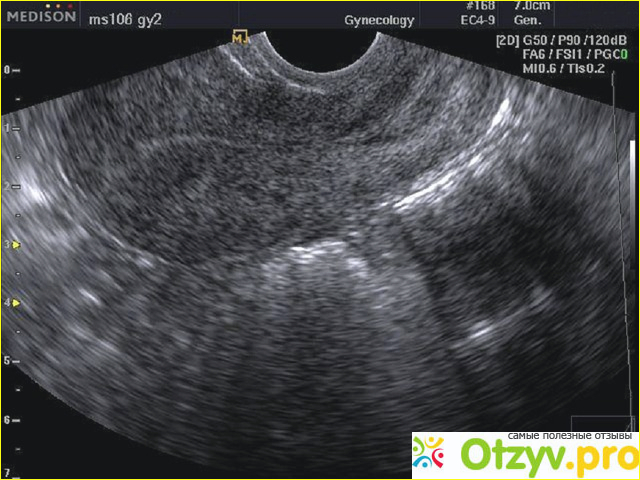

Ультразвуковое обследование матки

В настоящее время существует достаточно большое количество методов исследования женской половой сферы и среди них ультразвуковой метод является далеко не последним. Наоборот, он применяется очень часто и является достаточно информативным и показательным во многих планах. Гинекологи по этой процедуре могут поставить довольно точный диагноз, особенно если применяется современная аппаратура.

Наиболее часто проводится ультразвуковое обследование при изучении беременности, подозрении на внематочную беременность или ее приостановление (так называемая замершая беременность). Очень информативно ультразвуковое обследование при выявлении разного рода новообразований в матке – полипов, миоматьозных узлов, поликистозов яичников. Многие другие заболевания также часто выявляются при проведении УЗИ, правда порой необходимо в данном случае применение дополнительных методов.

Проведение диагностики при помощи ультразвука имеет разную информативность в зависимости от фазы менструального цикла. Желательно проводить исследования на первой фазе месячных, когда оболочка внутренняя наиболее истонченная и в ней наиболее легко выявить какие-либо вкрапления и новообразования. Очень важным моментом является ультразвуковое исследование области шейки матки. Если хоть как-то изменена структура этого места, то это должно насторожить гинеколога, поскольку при этом может иметь место воспалительный процесс, а то и вообще это может указывать на возможные новообразования. Наиболее распространенное заболевание шейки матки – это ее эрозия, которая может протекать как по доброкачественному, так и злокачественному типу. Ну а выявление новообразования, в частности опредеоение его формы можно только с применением ультразвука. Важно также проведение ультразвукового обследования при беременности, поскольку это указывает на то как протекает процесс беременности и имеются ли какие-либо отклонения от нормы.